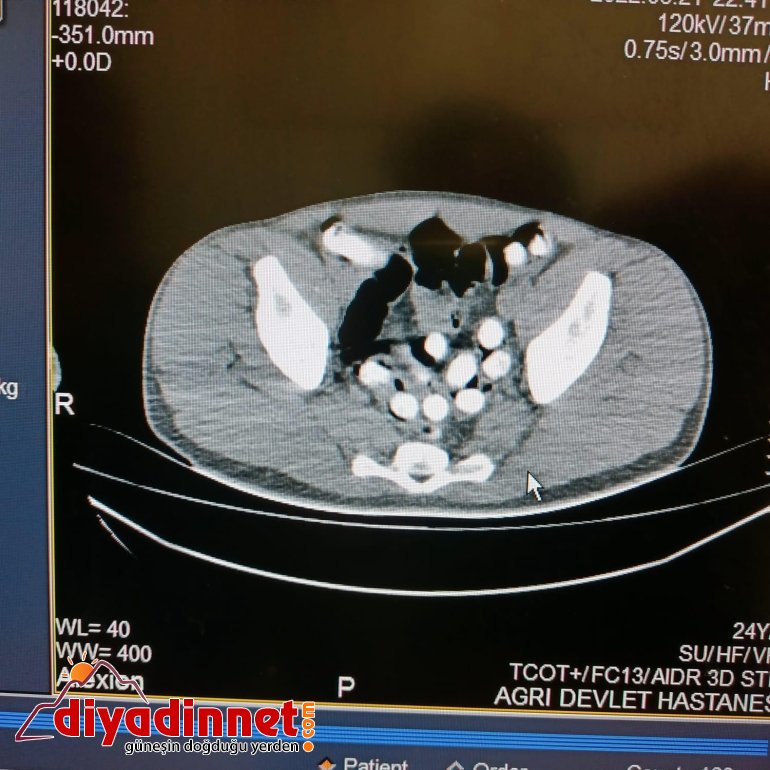

Ağrı - Ağrı Narkotik Suçlarla Mücadele Şube Müdürlüğü ekiplerince yol uygulamasında durdurulan bir yolcu otobüsünde yapılan aramada, otobüste yolculuk eden İran uyruklu Mehran Nazeri'nin şüphe üzerine üst araması yapıldı. Şahsın midesindeki şişliğin şüphe uyandırması üzerine kusturulması ile 6 adet kapsül halinde toplam daralı ağırlığı 62,35 gram gelen afyon sakızı ele geçirildi. Şahsın beyanı sonrası savcılıktan ek gözaltı süresi alınarak, hastanede çekilen röntgende mide ve bağırsaklarında başka kapsüllerin olduğu belirlendi. Şahsın vücudundan doğal yollarla çıkışı sağlanan toplam 102 kapsül halinde 1 kilo 126 gram afyon sakızı ele geçirildi. İran uyruklu Mehran Nazeri, Ağrı Savcılığınca tutuklanarak cezaevine gönderildi.